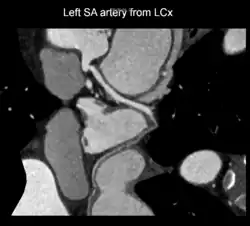

It arises from the right coronary artery in around 60% of individuals, from the left circumflex coronary artery in about 40% of individuals,[1] and in less than 1% of humans, the artery has an anomalous origin directly from the coronary sinus, descending aorta, or distal right coronary artery.

A left S-shaped sinoatrial artery, originating from the proximal left circumflex or LCx artery, has been described as a common variant in approximately 10% of human hearts.[5] This artery is larger than normal and supplies a good part of the left atrium, but also right-sided structures like part of the sinoatrial node and the atrioventricular nodal areas. In this variant, the artery courses in the sulcus between the left superior pulmonary vein and the left atrial appendage where it could be susceptible to injury during catheter or surgical ablation procedures on the left atrium, especially for atrial fibrillation ablation or open-heart cardiac surgery.